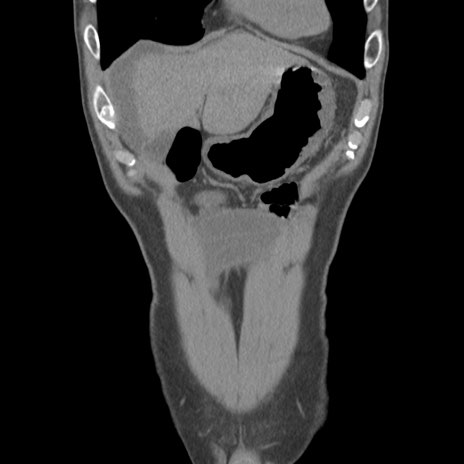

症例56 CT(冠状断像)

横断像